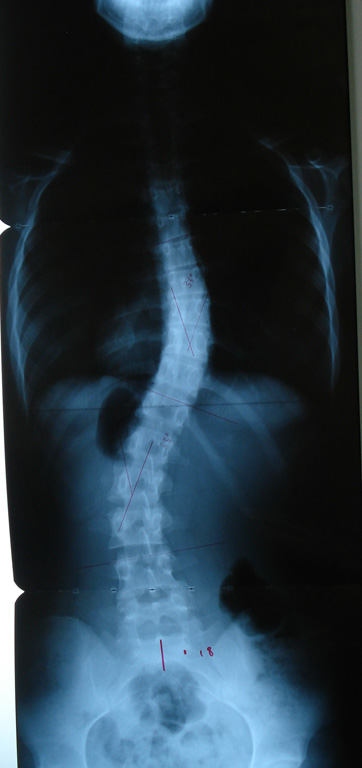

Grafilerle Skolyoz